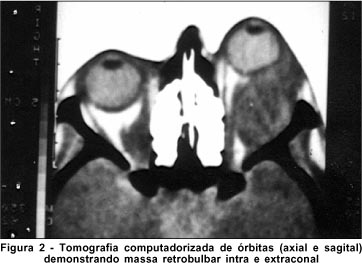

A tomografia computadorizada de crânio e órbitas revelou no plano sagital, grande imagem retrobulbar contrastante, grosseiramente arredondada, deformando pólo posterior do globo ocular com compressão do nervo óptico. No plano axial, massa bilateral que em OD é intracônica predominantemente e no OE, intra e extracônica. Havia heterogeneidade no interior da massa e múltiplas imagens hipodensas no plano coronal, sugerindo áreas de necrose (Figura 2).